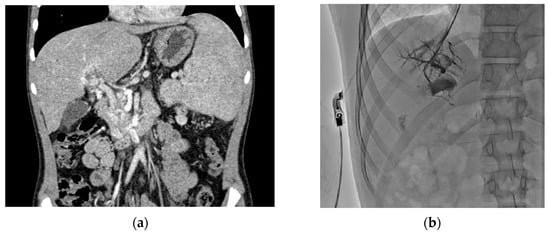

Shunt Surgery for Pediatric Prehepatic Portal Hypertension: A Single-Center Case Series

Background/Objectives: Management of prehepatic portal hypertension involves endoscopic and medical therapies with subsequent shunting if symptoms persist. Lately, surgical shunts, particularly the Meso-Rex shunt, are increasingly considered early in the disease course, offering benefits such as minimized hyperammonemia, improved somatic growth, and preservation of liver function. Our study evaluates post-operative outcomes after different surgical procedures in children with prehepatic portal hypertension. Methods: This single-centre retrospective case series included six children undergoing surgical shunting for prehepatic portal hypertension over a 5-year period. Medical records before and after surgery, followed for an average of 4.0 years, were analyzed. Results: Five patients underwent a Meso-Rex bypass, while one patient underwent a mesorenal shunt procedure. All cases showed clinically significant regression of esophageal varices six months post-surgery. Thrombocyte as well as leukocyte count significantly increased in five out of six patients during the long-term follow-up. Currently, five out of six surgically formed shunts (83%) continue to function normally. Conclusions: Our study supports early surgical intervention for improved long-term outcomes in managing portal hypertension, reducing complications like hypersplenism and variceal bleeding. Early consideration and ongoing monitoring are crucial for long-term success in children with portal hypertension. Full article

Figure 1